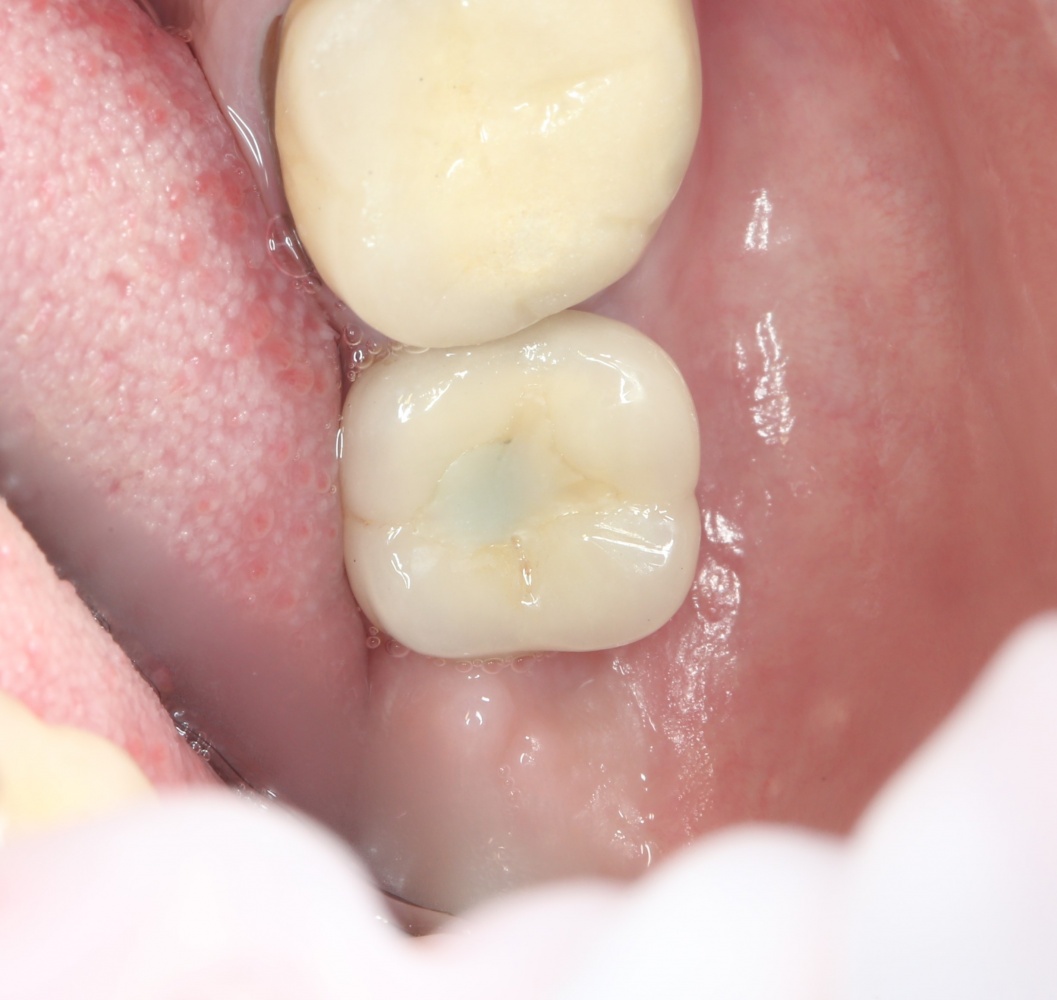

Рекомендации по установке имплантов. Для всех. Часть V.